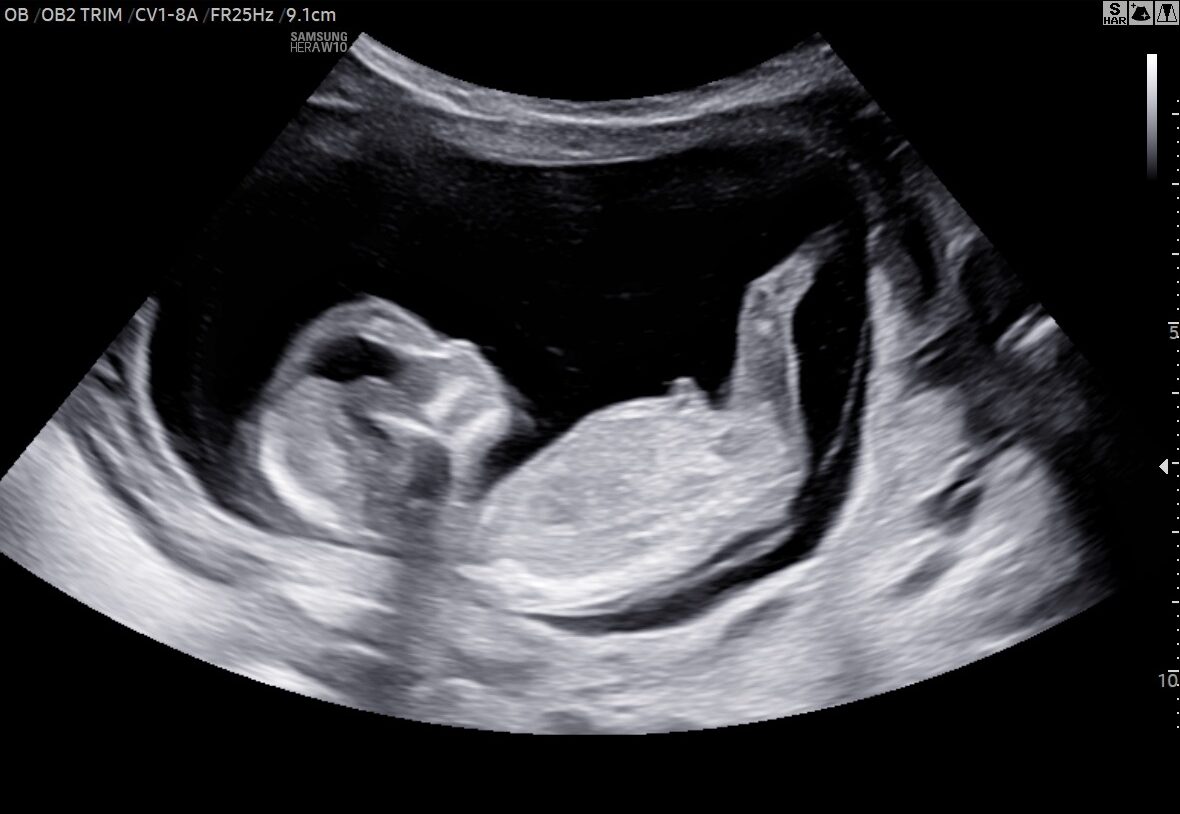

Ønsker I at se, hvordan jeres barn har det, og om det vokser, som det skal? Så kan I få lavet en tryghedsscanning her hos Den lille Jordemoder. Her ser vi på, hvordan barnet har det nede i livmoderen, og vi laver en vækstberegning, så I kan få et indblik i, hvordan barnet vokser. Derudover vurderer vi barnets placering og lytter til hjertelyden.

Ved en tryghedsscanning får I både printede billeder, en vækstrapport, optagelser af barnets hjertelyd og billeder overført til telefonen med hjem, som I kan kigge på efterfølgende.